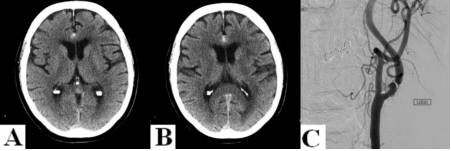

病例2:66岁女性患者,吸烟,既往高血压病史。因突发右侧眼眶周围疼痛、畏光和看到漂浮物而收治入院。头颅CT提示前纵裂SAH。次日DSA未见颅内血管异常,左侧颈内动脉近端可见粥样硬化斑块引起90%以上狭窄。6小时后,患者突然出现失语,头颅MRI-DWI图像显示左侧大脑中动脉供血区多发弥散受限病灶,提示左侧颈内动脉斑块脱落引起的继发性血栓栓塞。患者给予口服阿司匹林治疗,次日行左侧颈动脉内膜剥脱术,术后患者恢复顺利。

图2. A、B. 头颅CT示前纵裂局灶性SAH,大脑前动脉动脉瘤可疑;C-F. DSA显示左颈内动脉近端粥样硬化所致高度狭窄(C),但未发现颅内动脉瘤和血管畸形(D-F);下面两排图像为头颅MRI-DWI相,示左大脑中动脉供血区多发弥散受限病灶。